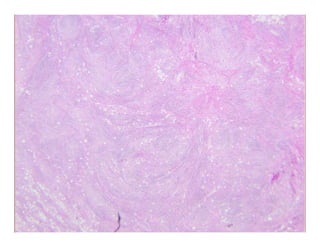

ParaffinomaParaffinoma

k S l i li lk S l i li laka…Sclerosing lipogranulomaaka…Sclerosing lipogranuloma

Special form of facticial panniculitis resulting from injection of lipiSpecial form of facticial panniculitis resulting from injection of lipi

(often paraffin) into subcutaneous tissue(often paraffin) into subcutaneous tissue

Well circumscribed noduleWell circumscribed nodulee c cu sc bed odu ee c cu sc bed odu e

? Swiss cheese appearance? Swiss cheese appearance

Bands of hyaline fibrous tissue between fat cells and cystic spacesBands of hyaline fibrous tissue between fat cells and cystic spaces